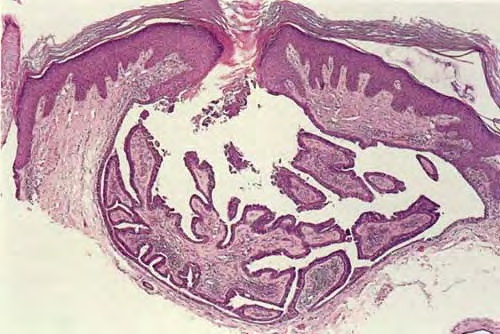

Syringocystadenoma = غدوم كيسي عرقي